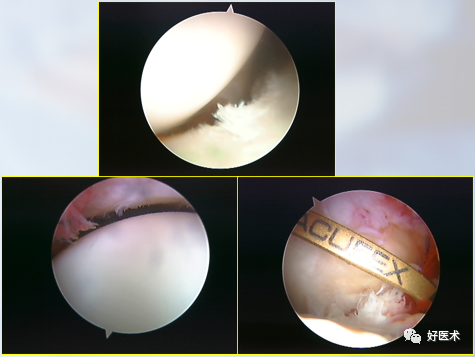

关节镜配套哪些关节镜技术速成诀窍_https://www.jmylbn.com_新闻资讯_第1张

在选用关节镜时,直径、长度、视角、焦距长度和视向角是关节镜最常用的指标。其中,直径(1.9mm,2.7mm,4mm)和视向角(0°,30°,70°)决定了关节镜的主要特征。

关节镜配套哪些关节镜技术速成诀窍_https://www.jmylbn.com_新闻资讯_第2张

1.关节镜下手术操作器械

关节镜配套哪些关节镜技术速成诀窍_https://www.jmylbn.com_新闻资讯_第3张